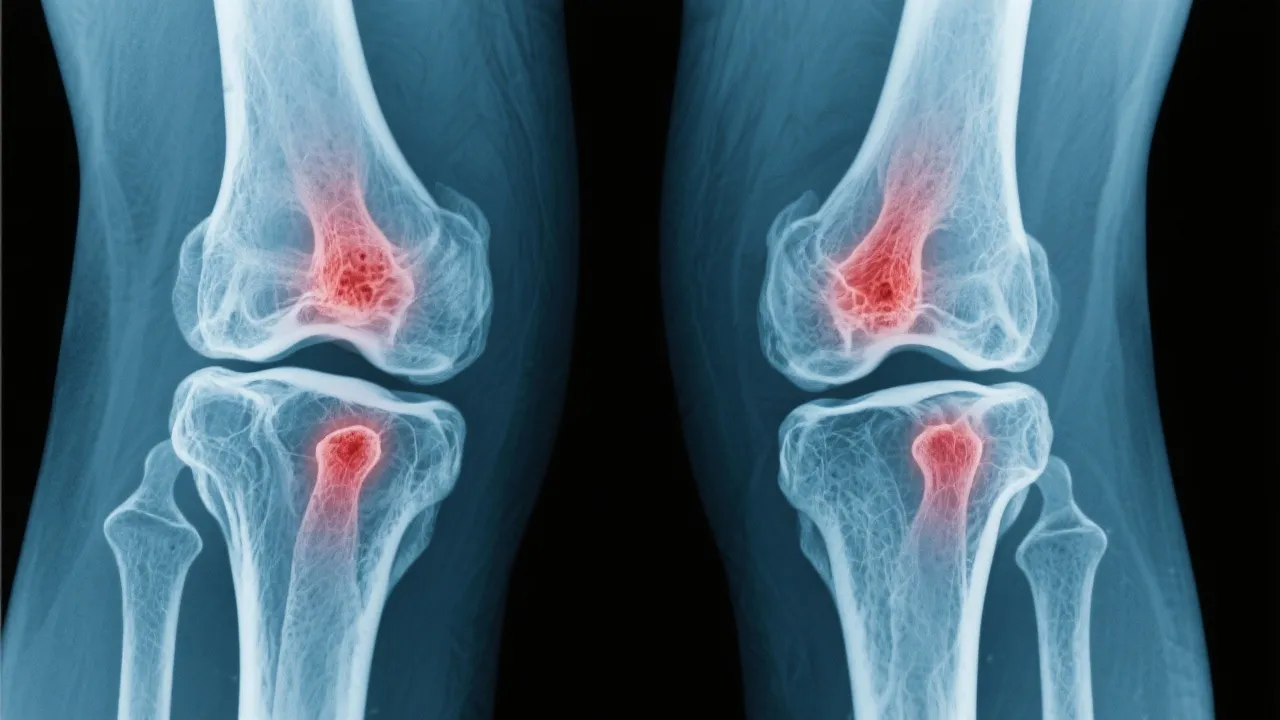

Understanding Arthritis and Its Impact

Arthritis, a term encompassing over 100 different conditions, primarily involves inflammation of the joints. This condition is characterized by pain, stiffness, and swelling, which can significantly impair daily activities and quality of life. As individuals age, the prevalence of arthritis increases, making it a common concern among the elderly, though it can affect younger demographics as well. Arthritis can manifest in various forms and can impact not only the joints but also other organs in the body, causing systemic symptoms and complications. It is crucial to understand the underlying pathophysiology of arthritis to better appreciate how it affects individuals’ daily lives and the complexities involved in its management.